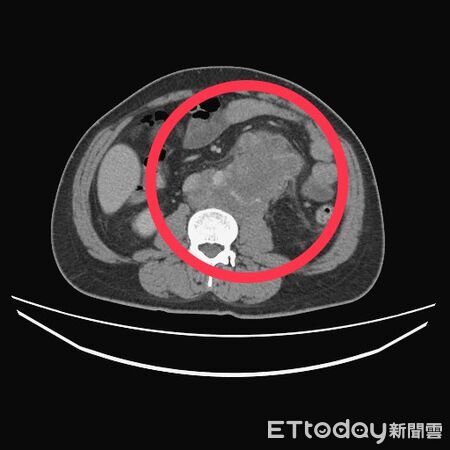

▲後腹腔也有一顆高達12公分的巨大腫瘤。(圖/醫師江佳駿提供)

衛生福利部台中醫院血液腫瘤科主治醫師江佳駿表示,患者入院後經X光及電腦斷層掃描檢查,結果發現,其體內已遭腫瘤「塞爆」,範圍涵蓋肺臟、肝臟及後腹腔。進一步追查發現,病源來自左側睪丸一顆5.5公分的惡性腫瘤,且後腹腔也有一顆高達12公分的巨大腫瘤,確診為睪丸癌末期且已廣泛轉移。